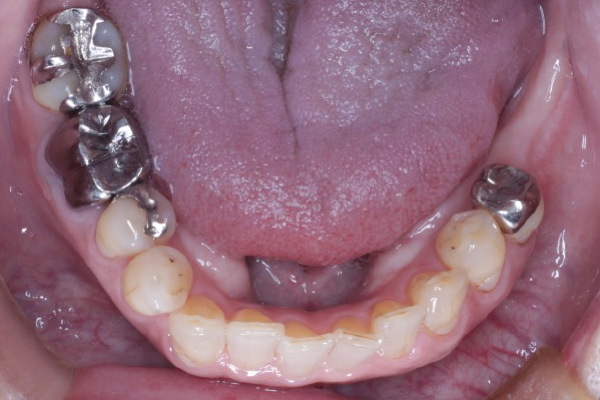

【お悩み】

奥歯を失ったまま過ごしていましたが、「手術が怖い」「本当に大丈夫なのか不安」という気持ちから治療に踏み切れずにいました。

【診断】

CT検査を行い、インプラント治療が可能な骨の状態であることを確認しました。

【治療内容】

治療前にしっかりと説明を行い、患者さまにご納得いただいたうえでインプラント治療を進めました。

【治療後】

治療後は違和感も少なく、「もっと早く相談すればよかった」とお話しされています。

【この症例のポイント】

不安を感じている方こそ、まずは状態を正確に知ることが大切です。

治療を受けるかどうかは、相談後に決めていただけます。